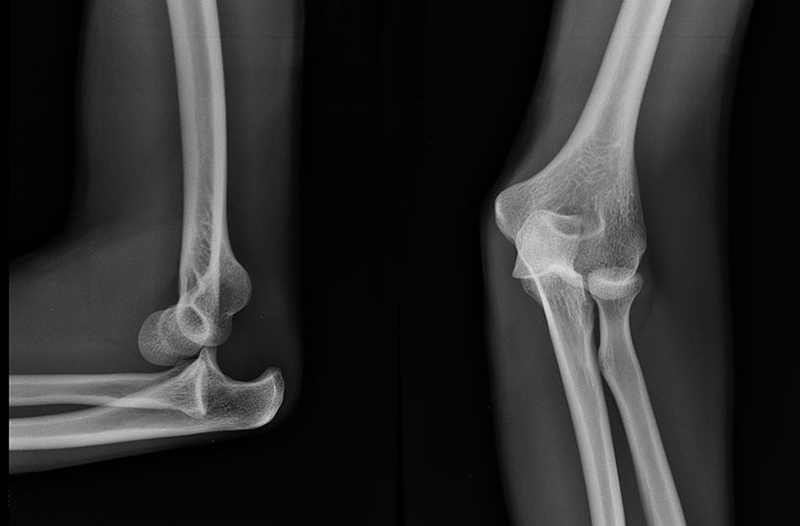

Khuỷu tay là một bộ phận quan trọng trên cơ thể của con người. Khớp khuỷu tay gồm có cấu tạo từ ba đầu xương hợp thành. Bao gồm đầu xương dưới cẳng tay, đầu xương trên trụ và xương quay. Mỗi xương này có một hình dạng, cấu tạo đặc biệt giúp cho khớp khuỷu tay có thể thực hiện các động tác gấp, duỗi… phức tạp. Đồng thời ở các xương của hệ thống khuỷu tay còn có các dây chằng liên kết chặt chẽ với nhau giúp cho xương luôn nằm đúng trục.

Trật khớp khuỷu tay là tình trạng các xương ở khớp khuỷu tay bị trật, lệch khỏi vị trí ban đầu do các nguyên nhân như ngã, chấn thương do các tác động từ bên ngoài và tai nạn giao thông.

Sau khi nắn trật khớp khuỷu tay, bác sĩ sẽ tiến hành bó bột cánh-cẳng-bàn tay rạch dọc, khuỷu gấp 90 độ, cẳng tay để ngửa. Thời gian bó bột sẽ kéo dài khoảng 3 tuần. Người bệnh cần chụp X-quang để kiểm tra sau khi bó bột vì chấn thương trật khớp khuỷu tay có thể tái phát trong quá trình bó bột. Sau khi tháo bột, người bị chấn thương nên chủ động gấp, duỗi khuỷu và tuyệt đối không xoa, nắn vùng khuỷu vì có thể gây vôi hóa sụn khớp.